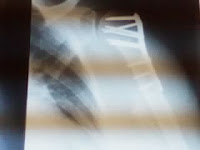

I will be setting off metal detectors from now on.....These were todays xrays...4 more weeks of immobility...then starting physical therapy..this sucks. It is too hot to be wearing this sling thingy. sigh...oh well